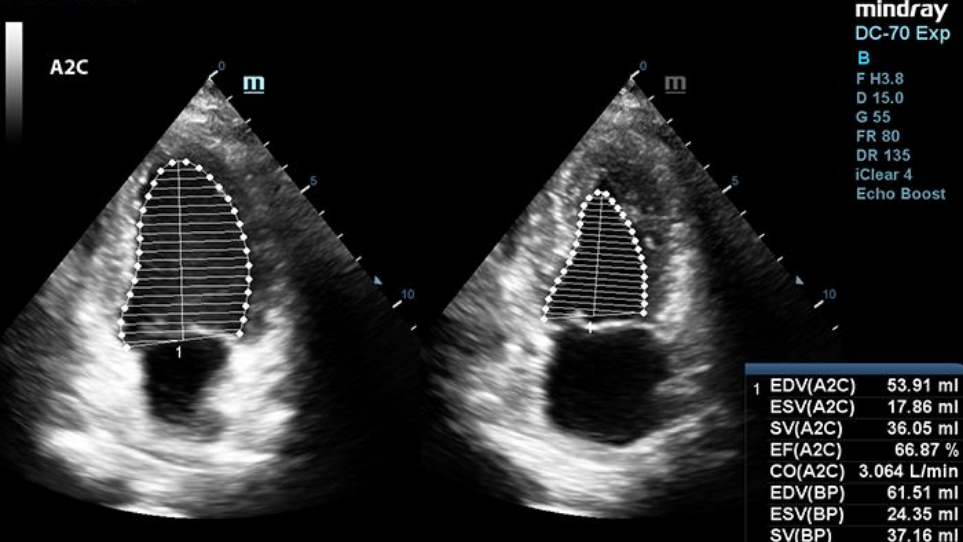

Auto EF

To help cardiologists evaluate left ventricle function more productively, X-Insight enables Auto EF, an intelligent way to recognize diastolic and systolic frames by analyzing 2D echo clips, with or without ECG. It also outputs a series of measurements alongside the image using the Simpson method, such as EDV, ESV, EF, etc.

During a cardiac exam, all the clinician needs to do is acquire the cardiac image and hit a few buttons. ECG is a plus but not a must. Auto EF will take care of the rest. It recognizes A2C or A4C and the border of endocardium immediately and identifies diastole and systole frames. With the calculation done accurately by its powerful algorithm, all the numbers you need are readily available for speedy and confident diagnosis in no time.

Coupled with fully automated operation, this user-friendly tool ensures accurate diagnosis, improved through-put, and reduced user dependency.